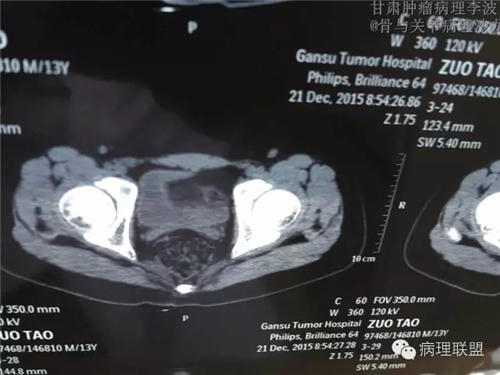

M/14 骶骨骨肉瘤-张惠箴讲解

病例由甘肃肿瘤病理 李波 提供,致谢。